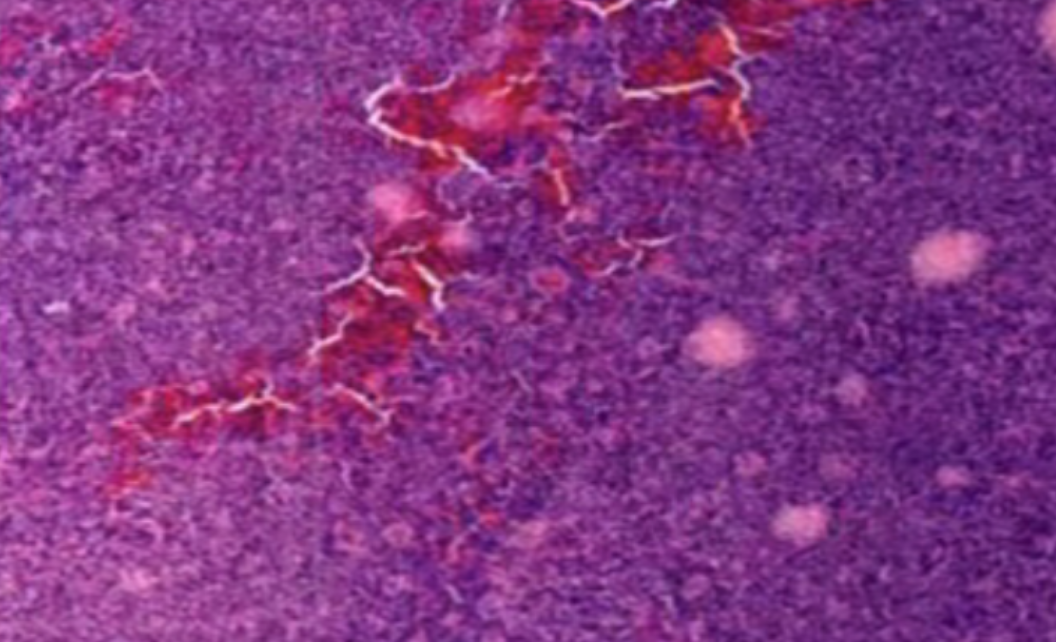

形成原因:切片经梯度乙醇处理后没有完全脱水,导致二甲苯透明、中性树胶封固后残留大量水分。 解决方法:首先移去盖玻片,用二甲苯溶解封固剂如中性树胶,再将切片置入无水乙醇内,待切片重新脱水完全后,用二甲苯透明处理,中性树胶封固。要注意所有用于脱水和透明的液体,在使用一定时间后,应及时更换。 二、细胞核呈红、棕色 形成原因:苏木精染色液过度氧化,切片在苏木精染液染色后返蓝不足。 解决方法:每次染色之前检查苏木精染色液的染色能力,发现苏木精染色液氧化过度应及时更换。此外,切片经苏木精染色后,要给切片以足够的蓝化时间,蓝化过程可用流水、温水、弱碱性溶液(如稀氨水或0.2%碳酸氢钠)等处理。 三、切片在脱蜡后出现大片白色斑点 形成原因:由于烤(烘)片温度太低,切片上的组织蜡膜在脱蜡前没有充分烤(烘)融化。或是因为切片在二甲苯液中停留时间不足,或二甲苯使用过久,造成的脱蜡不彻底。 解决方法:若是由于切片烤(烘)温度低所致,可以先用二甲苯去除切片上的封固胶,然后重新用二甲苯脱去切片上的石蜡,再进行后续染色。若是由于切片在脱蜡的二甲苯中停留时间不足或脱蜡二甲苯使用过久浓度不足所致,则需将切片退回到二甲苯中,停留较长时间,或更换二甲苯液体重新脱蜡,再入乙醇重新脱二甲苯,入0.5%盐酸水溶液褪色后,重新HE染色。 四、细胞核苍白暗淡,即苏木精染色太淡 形成原因:切片在苏木精染色液停留时间太短;苏木精染色液过度氧化,失去染色能力,不能再继续使用;分化步骤处理时间过长;固定不及时。此外值得注意的是,若骨组织细胞核暗淡,大多是脱钙过度造成的。 解决方法:切片重新染色。如果组织在酸性固定液(如Zenker、Bouin)或非中性缓冲甲醛液固定时间过长,细胞核染色能力将减弱,需增加其在苏木精染色液的时间,或用一些方法增加组织的嗜碱性,以改善细胞核的着色。例如,上述组织玻片可以使用Weigert铁苏木精染色液。如果组织是用Zenker液固定的,可将切片脱蜡后放在5%碳酸氢钠溶液3~4h,流水冲洗5min后染色。如果组织是用Bouin液固定的,可将切片脱蜡后放在5%碳酸锂1h,流水冲洗10min后染色。 五、细胞核过染,苏木精染液占据了细胞质 形成原因:玻片在苏木精染色液停留时间过长,或是切片太厚、分化步骤时间太短。 解决方法:如果不是因为切片太厚(用显微镜仔细上下微调,只有一二层细胞核层次),就需将切片进行脱色、漂白、重新染色,适当调整染色和分化时间。但如果确定是由于切片太厚导致的细胞核过染,则需要重新切片。 六、伊红着色淡 形成原因:可能是伊红染液pH值大于5,也可能是蓝化液残留过多,切片太薄,或是切片经伊红染色后在乙醇脱水时间过长。 解决方法:检查伊红染液pH值,必要的话,用乙酸将其调节在4.6~5.0之间,从而使伊红染色色彩艳丽。此外,确保每次蓝化步骤完成后,使用的弱碱性溶液被充分洗去,玻片上没有残留的弱碱性溶液。最后,检查切片的厚度,且脱水时不要让切片在低浓度乙醇中停留时间过长,因为含水多的低浓度乙醇会将切片伊红的颜色分化掉。 七、细胞质过染、分色不足 形成原因:伊红染色液浓度太高,特别是存在焰红燃料、四溴四氯荧光素钠。切片在伊红染色时间过长,或是切片在伊红染色后经乙醇脱水步骤时时间太短,而使乙醇分化伊红的作用不能产生,都能够使细胞质过染。 解决方法:适当稀释伊红染色液,减少伊红染色时间,或使切片在乙醇脱水等步骤时,停留时间相对均匀。同样,也要检查切片的厚度是否合适。 八、切片中出现蓝黑色沉淀物 形成原因:苏木精染色液中的金属膜黏附在玻片上。 解决方法:染色前仔细过滤苏木精染色液,建议使用半氧化苏木精染色液,如Gill苏木精染色液,可以避免过多的金属膜产生。 九、光镜下切片某些区域难以聚焦 形成原因:盖玻片上可能有封固切片的封固剂。 解决方法:移去盖玻片,重新用干净的盖玻片封片。检查切片封片方法,是人工手工封法,还是机器自动封法,如有问题及时调整。 十、封固剂从盖玻片与载玻片之间的缝隙回缩 形成原因:盖玻片弯曲或不平整,或是封固剂含二甲苯过多,稀释过度。 解决方法:移去盖玻片,重新找一张盖玻片,用干净的封固剂封片。如用手工封片法,保证在封固结束时,封固剂容器盖子为紧闭状态。且尽量使用小的容器盛装封固剂,一旦封固剂太黏稠,就可以选择废弃。 十一、细胞核呈灰蓝状态 形成原因:可能由于组织处理温度过高、过热,在液体石蜡中停留的时间过长。或是固定时间太短后,直接在高浓度的乙醇中进行了脱水处理。 解决方法:理论上来说,仅在组织浸蜡步骤才进行加热,组织不能在热蜡液中停留太久。如果由于某些原因不能进行下一步包埋处理,可将组织连同塑料包埋盒一并放置在室温空气中,冷却凝固,以备包埋。待需要包埋时再重新加温直至石蜡融化即可。组织在处理前必须确保固定良好,脱水最好能从低浓度的乙醇开始。 十二、类色素的点状结晶和黑色光滑细胞核 形成原因:这种裸核改变是因为切片封片前放置在空气中的时间太长,以至于二甲苯挥发,切片干燥。 解决方法:移去组织切片上的盖玻片和封固剂,重新处理。将切片水洗数分钟,然后重新脱水、透明、封固。封片过程中要保持组织切片的轻度湿润,尽量不要让其干燥。 十三、染色过淡或过浓 解决方法:如果染色过淡,可以增加染色剂的浓度、延长染色时间或更换新鲜的染色剂;如果染色过浓,则应减少染色剂的浓度或缩短染色时间。 十四、切片出现叠加褶皱 形成原因:新购买的玻片洁净度不够、用镊子撑开切片时操作不够熟练未能平整伸展,或玻片表面有油脂,切片粘贴不牢。另外,烤片时间不足、烤片温度过低或切片过厚造成切片脱落,都会造成重叠或有皱褶的情况。 解决方法:新购买的玻片最好能用硫酸清洁液浸泡一晚,然后流水冲洗干净。在适宜的温度下烤片时间宁长勿短,保证有充足的烤片时间和温度。另外,切片刀要锋利,才能切出厚薄适宜的切片,保证切片不会因为过厚而脱落。 十五、组织残缺不全或有刮划痕迹 形成原因:组织残缺不全是由于切片时修整蜡块时深度不够、组织没有全部暴露于切面。切片的刮划痕迹是由于切片刀的刀锋有缺口、包埋的组织有异物,或是钙化组织、骨组织及包埋石蜡有沙粒造成的。 解决方法:修整蜡块时保证组织块全部暴露于切面,切片时保证切片刀的锋利没刀口。同时在组织取材时去除手术异物和钙化组织。最后,骨组织要完全脱钙,这样可以保证切片的完整和平整美观。 *注:由于实验中导致结果出现误差的原因多种多样,以上内容仅供参考,具体根据实际情况进行判断。